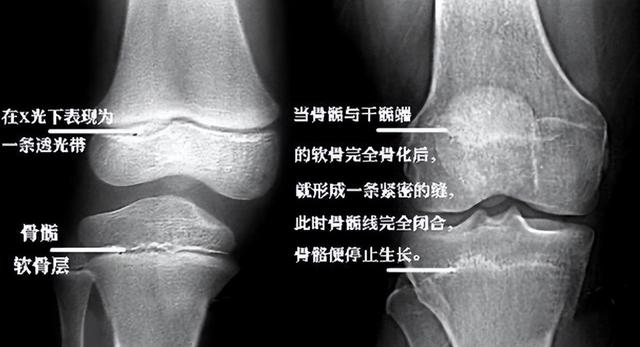

骨骺线是骨骺板的截面图像,在儿童拍摄的x光片上表现为一条透光带。简单来说,就是一个细条形状的黑影。

随着孩子的成长,骨骺线会不断硬化,最终变成骨头。在这期间,孩子的四肢不断的变化,帮助孩子长高。

因此,一般以骨骺线是否闭合为孩子是否停止长高的信号。